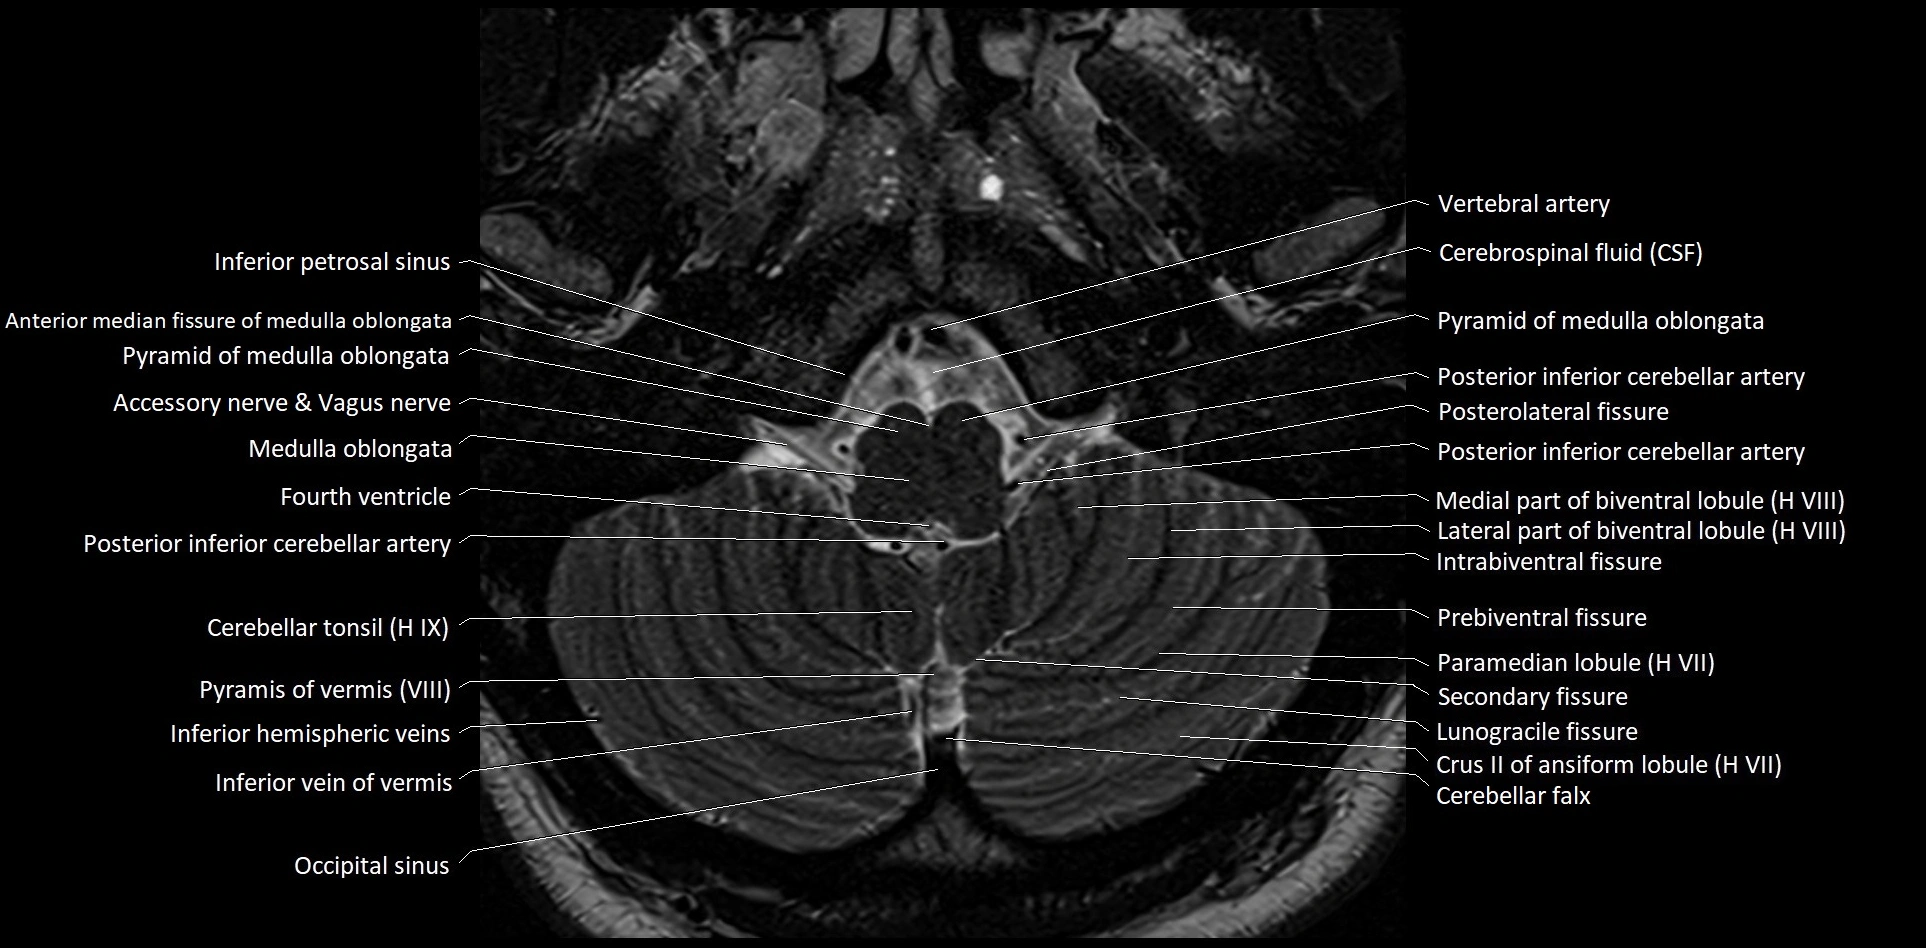

MRI images